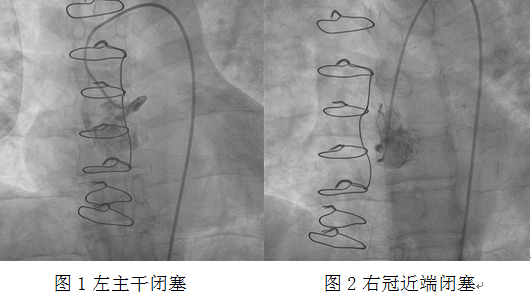

心血管介入團隊立即予患者冠狀動脈造影。造影顯示左主干閉塞、右冠狀動脈近端閉塞。此時患者表情淡漠,血氧飽和度75%,為心源性休克狀態(tài)。考慮患者為橋血管急性閉塞,如不立即開通閉塞血管,患者有生命危險!

介入團隊經(jīng)過努力,發(fā)現(xiàn)前壁至右冠狀動脈的靜脈橋血管急性閉塞,嘗試正向開通原血管困難,此時患者血氧飽和度進一步下降,遂決定對急性閉塞的靜脈橋血管行急診介入治療。